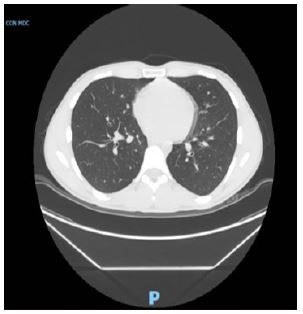

A 19-year-old male (BMI 22 kg/m², ASA I) presented for elective laparoscopic appendicectomy. The procedure was performed under general anesthesia using propofol, rocuronium, and sevoflurane. Intubation with a 7.0 mm endotracheal tube and intraoperative course were uneventful (Figure 1).

Figure 1: Chest CT with IV contrast before surgery.